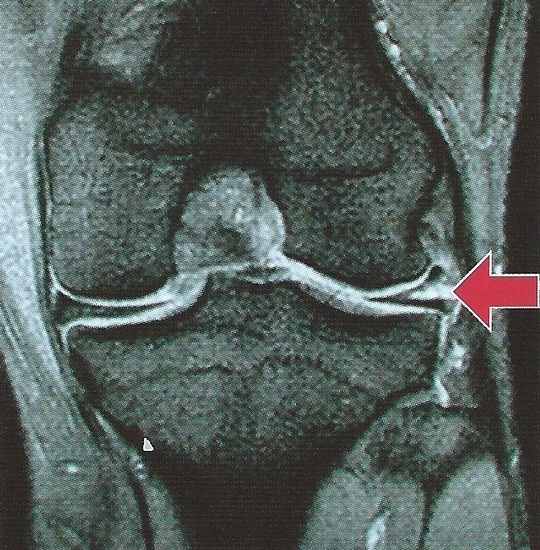

外側半月の縦断裂